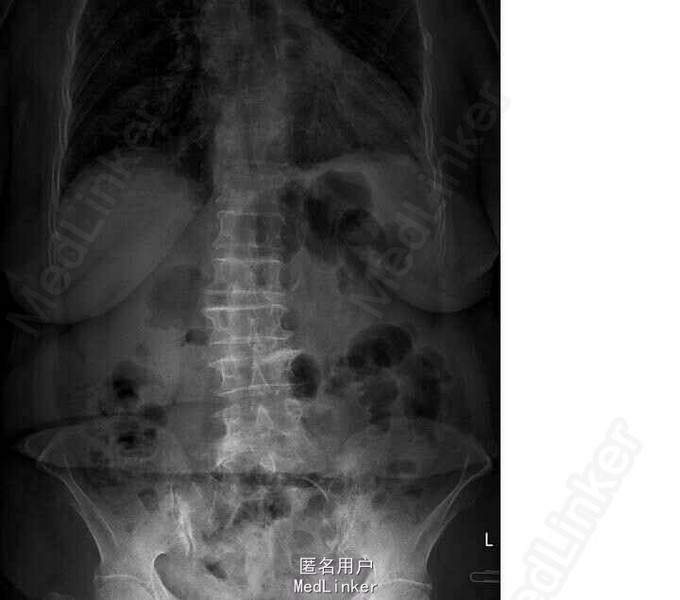

查体:胸腰段明显压痛及叩击痛。双髂嵴处压痛明显。 X线片示T11楔形变

诊断:胸椎压缩骨折(T11) 局麻下行椎体成形+活检术